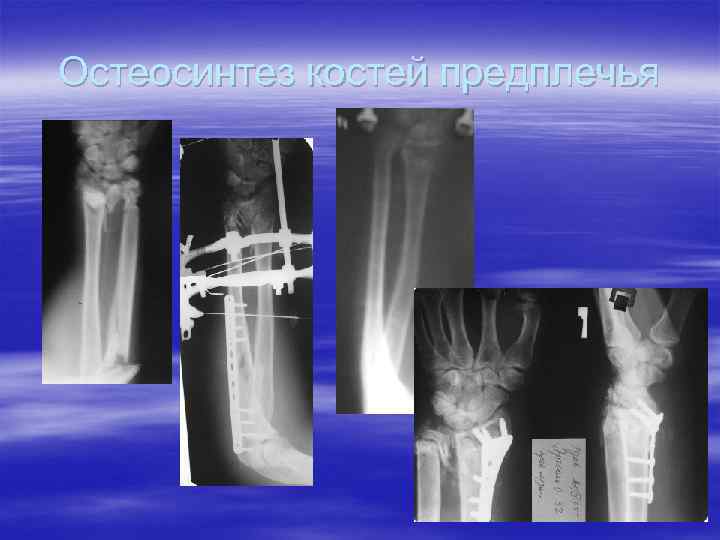

Остеосинтез костей предплечья